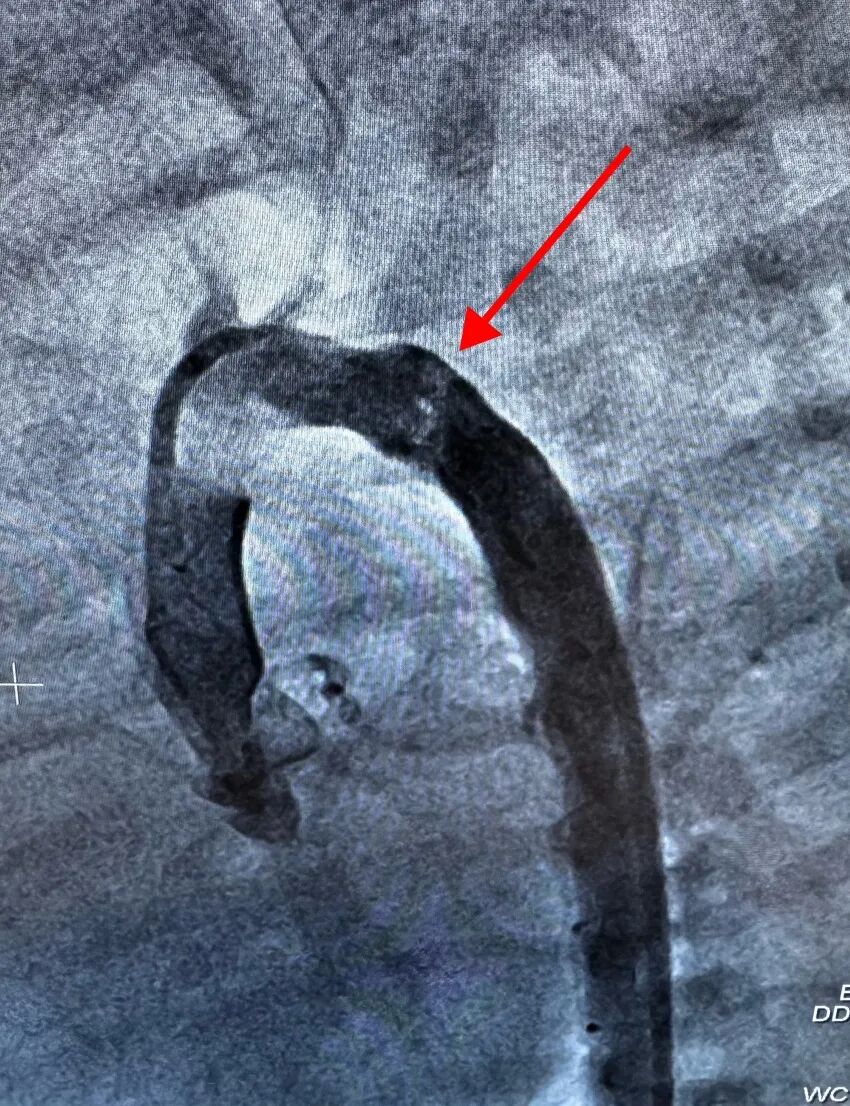

主动脉最狭窄处由1mm扩张到近6mm,压差几乎为零,血流恢复了畅通,那条被堵塞的“生命主干道”终于被成功打通。手术成功!